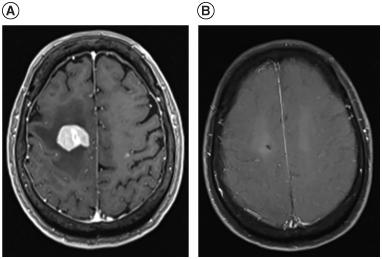

Background: Treatment for refractory or relapsed primary CNS lymphoma (r/r PCNSL) is challenging. Salvage whole-brain radiation therapy (WBRT) is an option but has a short duration of disease control, so additional treatment modalities are warranted. Case: A 75-year-old female with r/r PCNSL who had multiple progressions after multiple lines of treatment underwent salvage WBRT. The patient received ibrutinib, a Bruton's tyrosine kinase inhibitor, as maintenance therapy for 18 months following WBRT with the intention of increasing survival duration after salvage WBRT. She survived 81 months from diagnosis, including 57 months after completion of WBRT. Conclusion: This case presentation describes the experience of using ibrutinib as maintenance therapy in treating r/r PCNSL after salvage WBRT.

Abstract Image